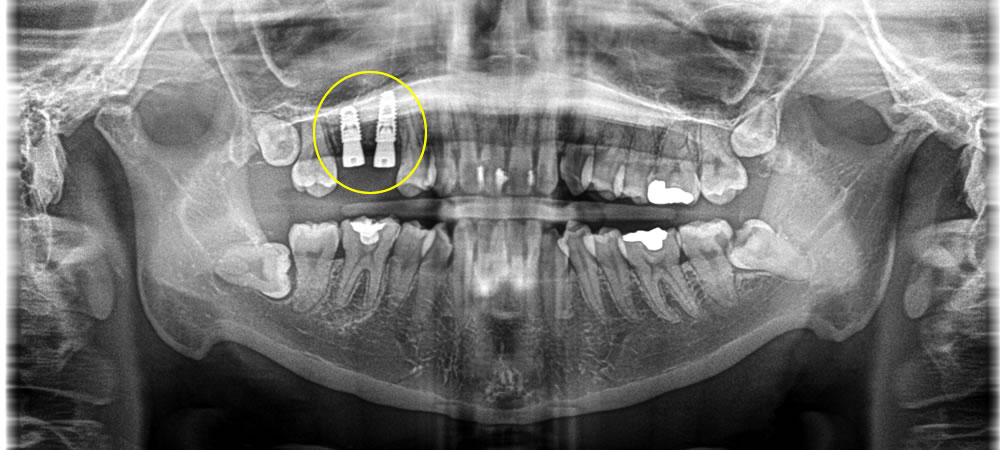

上部構造の装着・治療完了

術後は元々あった歯と同じようにしっかりと噛むことができるようになり、審美的にも機能的にも大変満足していただいております。